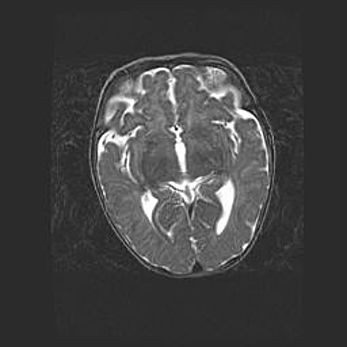

Церебральная ишемия II.

Возраст: 5 дней

Вес: 3400 г

Пол: женский

Окружность головы: 35 см

Срок гестации: 39 недель

Церебральная ишемия – это заболевание, характеризующееся недостаточностью (гипоксией) либо полным прекращением (аноксией) снабжения мозга кислородом по причине закупорки одного или нескольких сосудов. Это приводит к  что метаболическим расстройствам различной степени тяжести в тканях головного мозга, развитию коагуляционных некрозов и гибели нейронов.